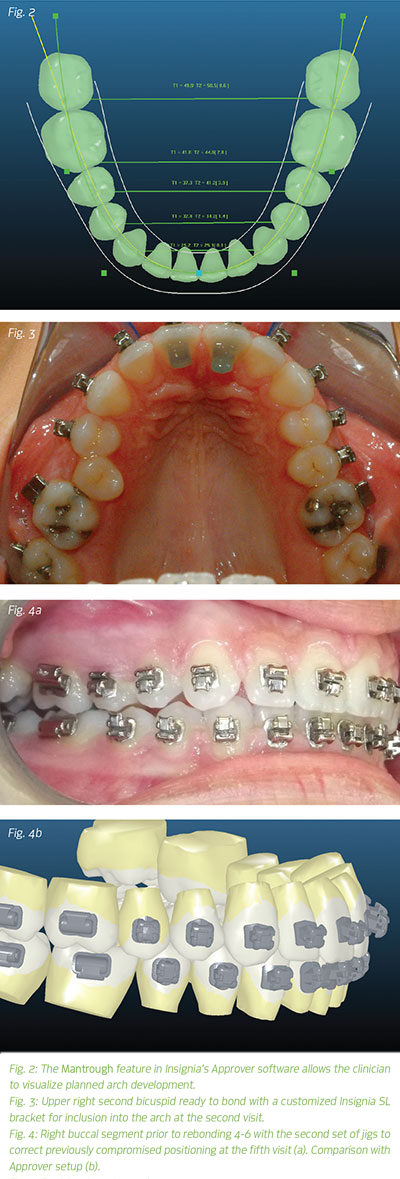

The plan was to treat the patient non-extraction by employing a system of 3D treatment software (Fig. 2) and customized passive self-ligating appliances (Insignia Custom SL, Ormco, Orange, California) with upper anterior bite turbos to disarticulate the arch and develop it transversely, thereby alleviating the crowding and correcting the crossbite while employing light CL II elastics for A/P correction.

The upper right second bicuspid alignment was improved (Fig. 3) by use of an open coil spring between the upper right first bicuspid and first molar with a ligature tied to a bonded button on the second bicuspid. The button was then replaced at the second visit with a bonded bracket using the Insignia provided single tooth bonding jig. At the fifth/interim panograph appointment (which I take after the .018 x .025in CuNiTi wires have been in place for six weeks), the upper right 4-6 were rebonded with the jigs to correct the placement that had been previously compromised by crowding (Fig. 4). Correction of the A/P was also begun with 2oz, 5/16in CL II elastics, maintained until debonding. Treatment progressed through the next two appointments with debonding and a thermoformed retainer delivered at the final appointment.

At the interim panograph appointment, I review roots for possible bracket repositioning as well as assess whether there are any discrepancies between the digital Approver setup and the "real life" tooth positions (Fig. 6). To address discrepancies, I make a determination about whether the genesis of the issue was the Approver setup or bracket placement.

If, upon review, the "real life" tooth positions are different from the digital setup, I made a mistake in bracket placement and will use the placement jigs to reposition brackets. Sometimes, however, comparing the teeth in "real life" to the Approver software reveals a setup error. If I approved a setup that included an error, I will reposition brackets by hand in the appropriate position. There is a bit of a learning curve in understanding how the virtual setup translates to tooth positions in the mouth. The Approver software dictates bracket fabrication and placement exactly as I design setups. Clinical experience yields improved skill in setting up cases in the digital world. Excellent setups produce excellent results and efficient treatment. When learning Insignia, take the time to explore the software and become an expert in Approver setups.

Incorrect bracket placement is usually a result of an inability to position the placement jigs for sufficient draw given the crowding. Insignia comes with two sets of jigs. The first set, used for initial bonding, typically has as many teeth as possible per segment for bonding efficiency. Each jig in the second set is cut for individual teeth with deeper occlusal anatomy.

When it is impossible to place specific brackets precisely because of crowding and/or rotations, the second set of jigs will allow you to refine placement. The second set is also used to rebond loose brackets during treatment. The deepened occlusal anatomy on the second set offers a more precise feel for the correct placement of the jig on the tooth. Insignia provides paperwork before bonding that indicates if any brackets will need to be rebonded later due to probable jig fit issues. Insignia cases are now accompanied by redesigned jigs made of clear material to provide an enhanced fit that assists in first-time bracket placement and ease of curing. Integration with Ormco's new Lythos digital impression system offers a precise and efficient alternative to PVS impressions and should quickly become the modality of choice for capturing pretreatment dentition.